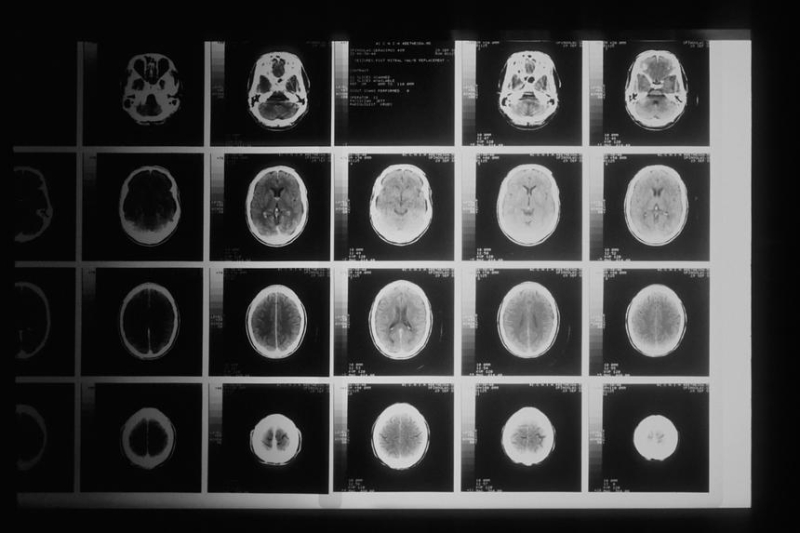

Как показало новое исследование, те, кто живёт в районах с низким социально-экономическим статусом, гораздо чаще страдают от инсульта, чем люди, которые живут в районах с более богатых районах. Об этом говорится в статье, опубликованной в Journal of Stroke and Cerebrovascular Diseases.

В рамках нового исследования учёные проанализировали записи больниц и смертей в Тасмании за период с 2007 по 2020 год. Они обнаружили, что у людей из группы с самым низким социально-экономическим статусом вероятность столкнуться с инсультом была на 33% выше, чем у тех, кто относился к группе с самым высоким социально-экономическим статусом.

Особую обеспокоенность вызывает факт, что влияние более низкого социально-экономического статуса на возникновение инсульта было сильнее выражено у молодых. Также исследование показало, что факторы риска инсульта, такие как диабет, высокое кровяное давление и болезни сердца, чаще встречаются в неблагополучных сообществах.